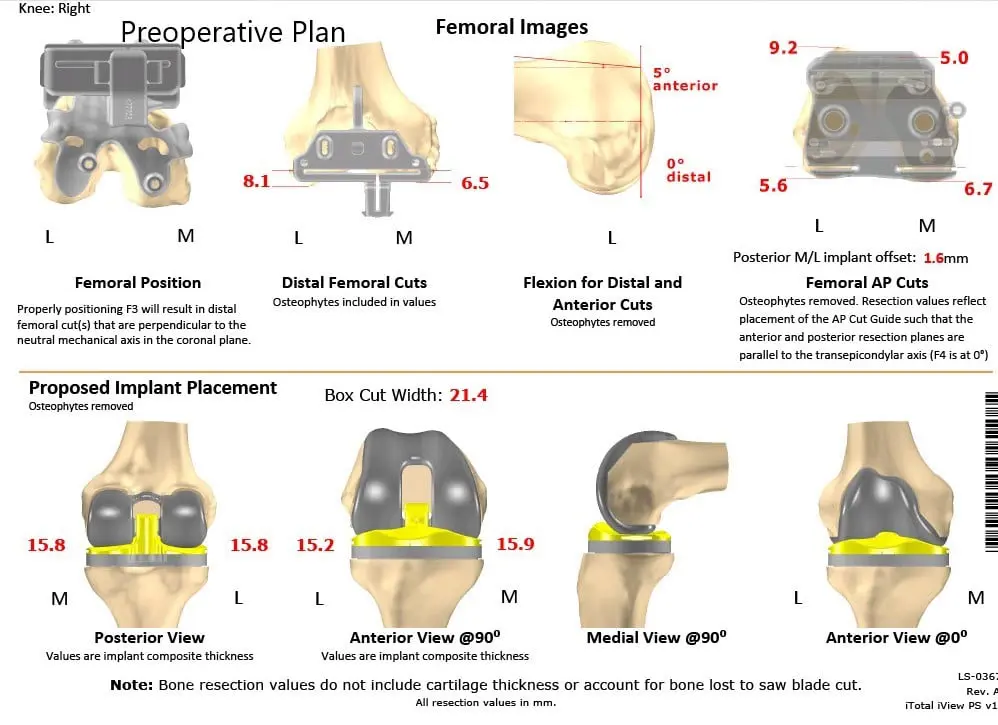

Further CT scan of the right knee was obtained prior to the surgery. The information was utilized to create a 3D model of the patient’s knee anatomy. Unique patient-specific implants were then constructed utilizing the information of anatomy and biomechanics. Custom disposable jigs and instruments were 3D printed to match patients’ natural anatomy of the knee. A customized preoperative plan was created for accurate bone cuts and biomechanics.

Complete Orthopedics patient-specific surgical plan for a right knee custom arthroplasty in an 83-year-old male (scan 2)